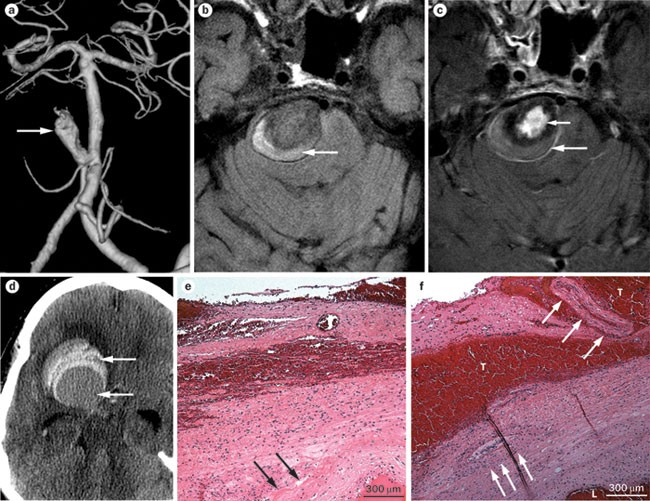

Intracranial Aneurysms From Vessel Wall Pathology To Therapeutic Approach Nature Reviews Neurology